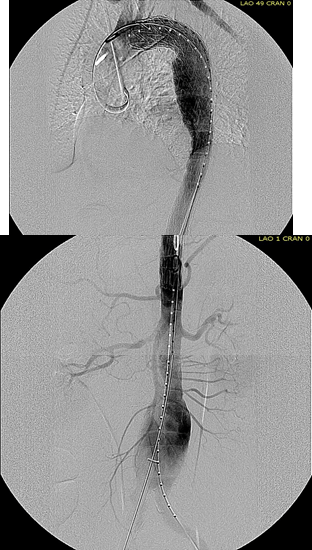

The patient was operated on in a hybrid endovascular OR suite. A right groin incision was made to expose the common femoral artery for endarterectomy and left common femoral access was achieved for angiographic access, but also to place a wire across the occlusion into the common femoral artery.

All actions on the external iliac artery plaque are done with an up-and-over wire, allowing for swift action in the instance that arterial perforation or rupture occur. This event is exceedingly rare when the operation is well planned. With this kind of access, an occlusive balloon or repairing stent graft can be rapidly delivered.

The common femoral endarterectomy is done from its distal most point and the Vollmer ring is used to mobilize the plaque. A Moll Ring Cutter (LeMaitre Vascular) is then used to cut the plaque.

The plaque is extracted and re-establishes patency of the EIA.

The plaque end point is typically treated with a stent -in this case, the common iliac plaque was also treated.